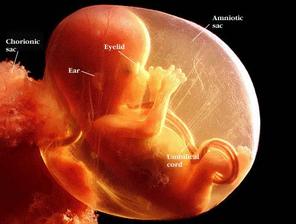

29.4. druhá KO u dr 7+3, 12,3mm a srdíčko bije

23.5. pro průkazku + odběr krve + utz 11+0 mimisek 4,2cm